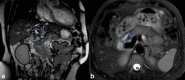

The Abernethy malformation consists of a congenital extrahepatic portosystemic shunt and is believed to be extremely rare in humans. The potential implications of abnormal portovenous shunting and decreased hepatic portal flow are numerous and potentially serious. Although congenital extrahepatic portosystemic shunts are increasingly suspected and diagnosed in specialized centres, much of their clinical presentation and natural history is not fully understood. Symptoms of portosystemic shunt are mainly caused by increased levels of ammonia, which lead to signs of encephalopathy. Therapeutic options depend on the type of shunt and its clinical course, so the classification of the congenital portosystemic shunt is a key finding in these patients.